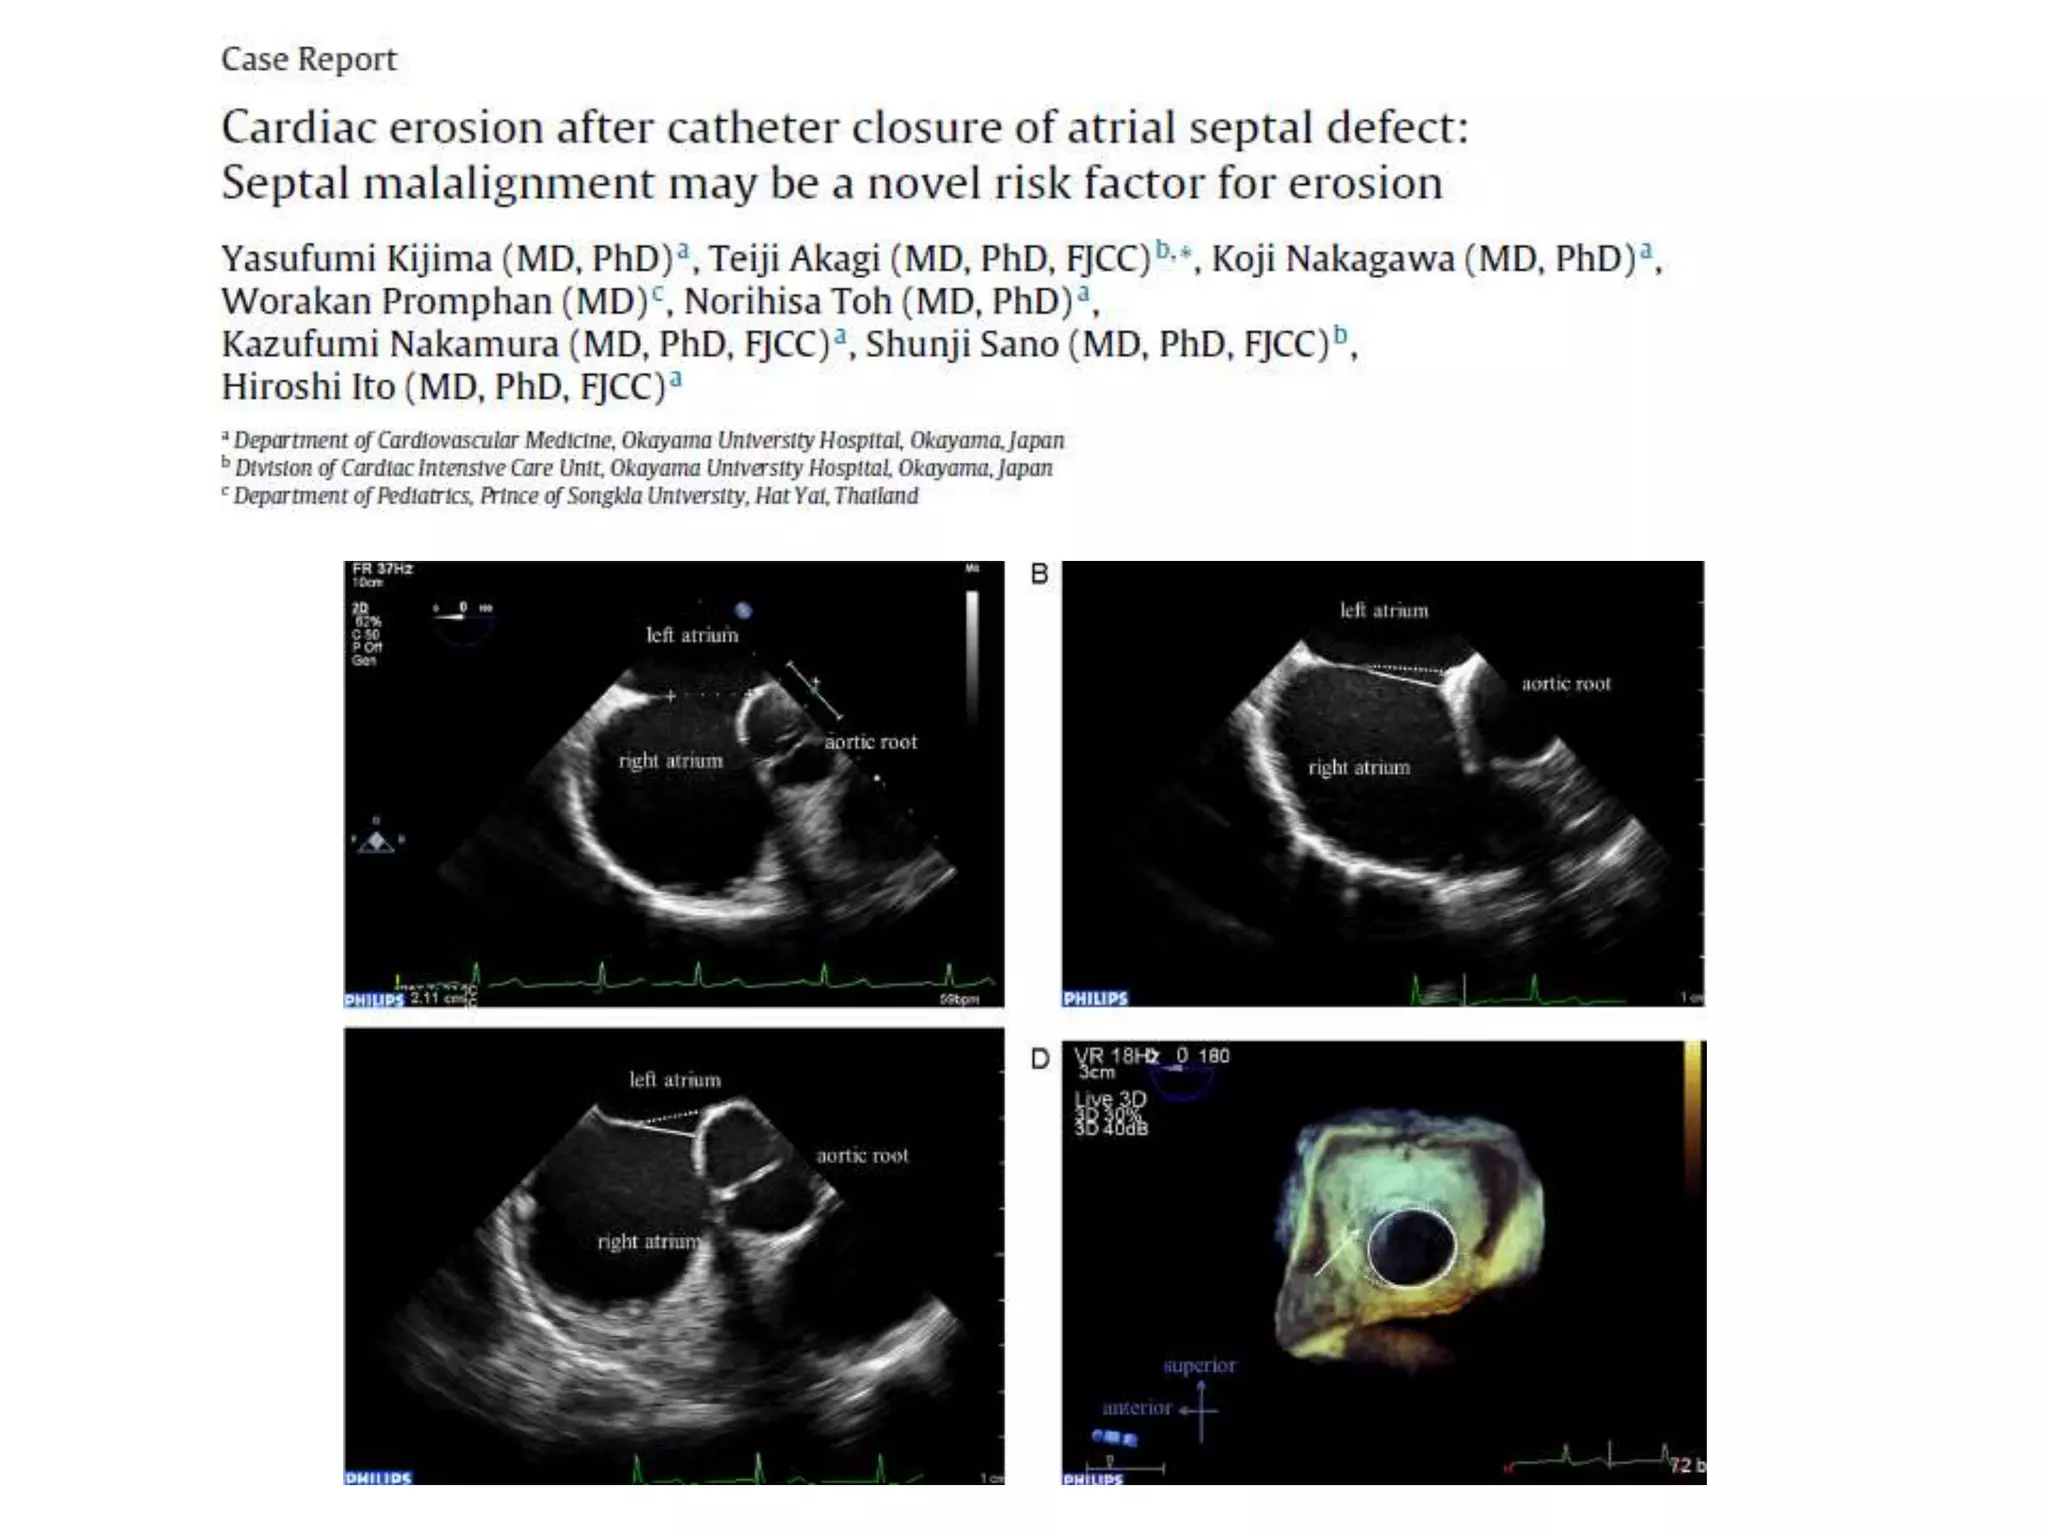

RIMS OF ASD

ASD IN VARIOUS PHASES OF CARDIAC CYCLE

RIMS OF ASD ASDIN VARIOUS PHASES OF CARDIAC CYCLE